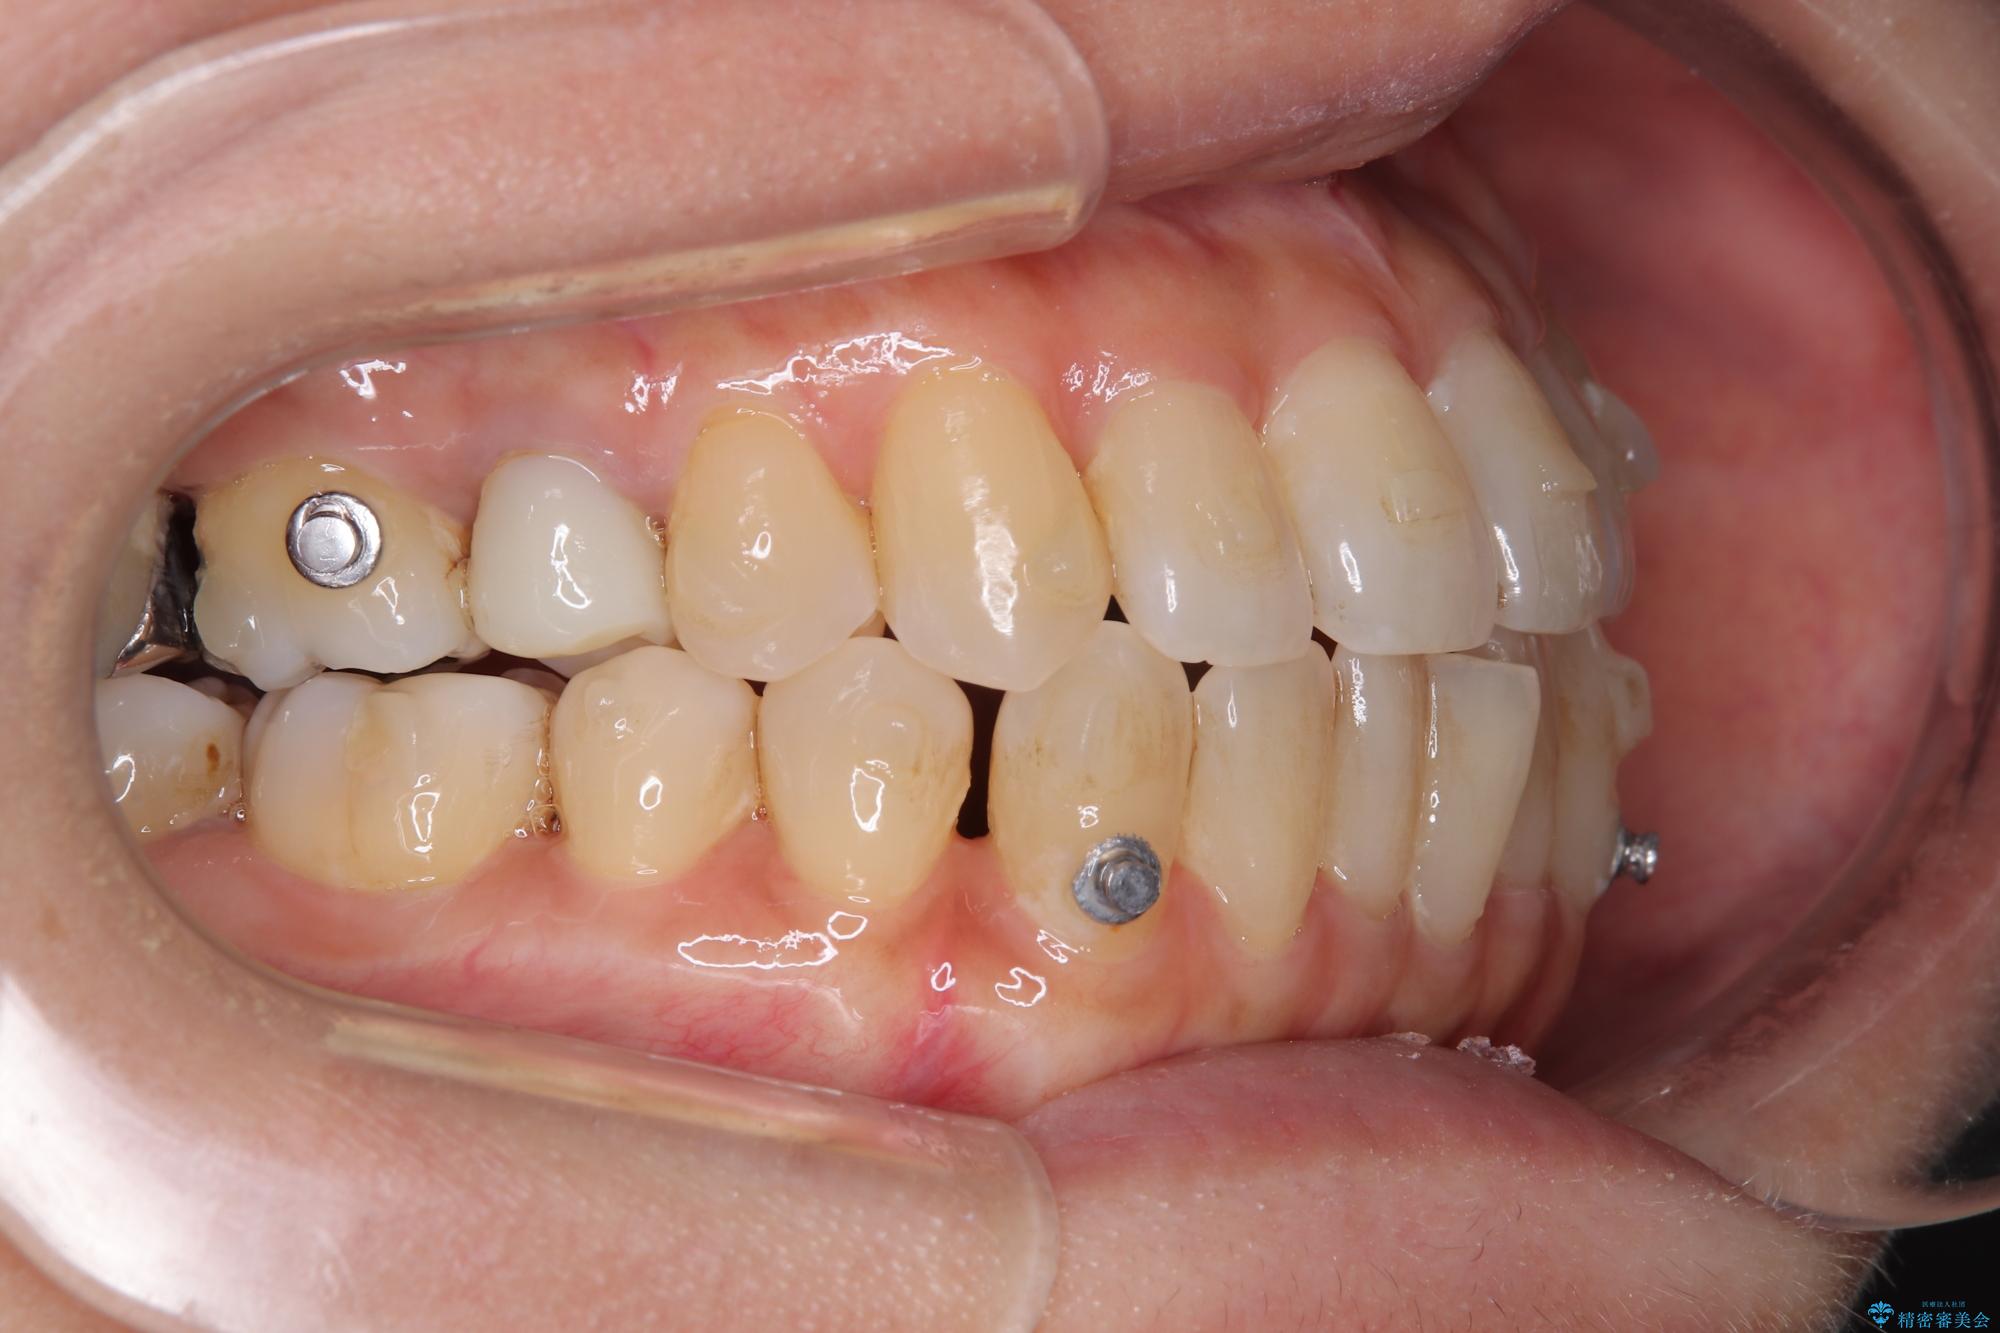

受け口傾向の骨格であり、前歯はクロスバイトまたは切端咬合となっており、下顎を中心に歯列全体の後方移動を行い、IPR(歯と歯の間を削る)によってデコボコが解消するように設計し、インビザラインにより治療を行うこととしました。

受け口傾向のインビザライン矯正は比較的治療を行いやすいため、きれいに仕上げることができました。舌の突出癖が顕著であったため、改善のためのトレーニングをしっかりと行っていただきました。